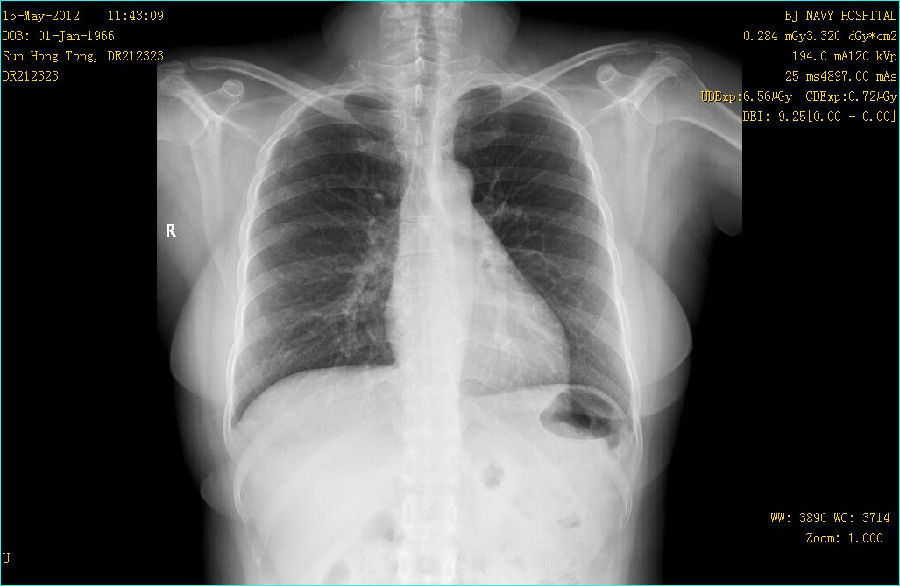

病史: M,46Y 病人主诉:常规体检 曝光参数 120KV;194mA ; 25ms ; 0.284mGy 常规胸部平片:

病例点评: GE公司的双能成像检查采用可以快速读取的X线平板探测器,由X射线球管间隔约150ms进行低能(低kVp)和高能(高kVp)两次曝光。采集到的图像经过图像工作站快速处理产生一组3幅图像:标准平面图像,软组织图像和骨骼(钙化)组织图像。这种双能量DR检查对于改善肋骨后面重叠区域的非钙化结节的能见度非常有效。同时对在肋骨间和超过骨组织钙化的结节能更好地显示。